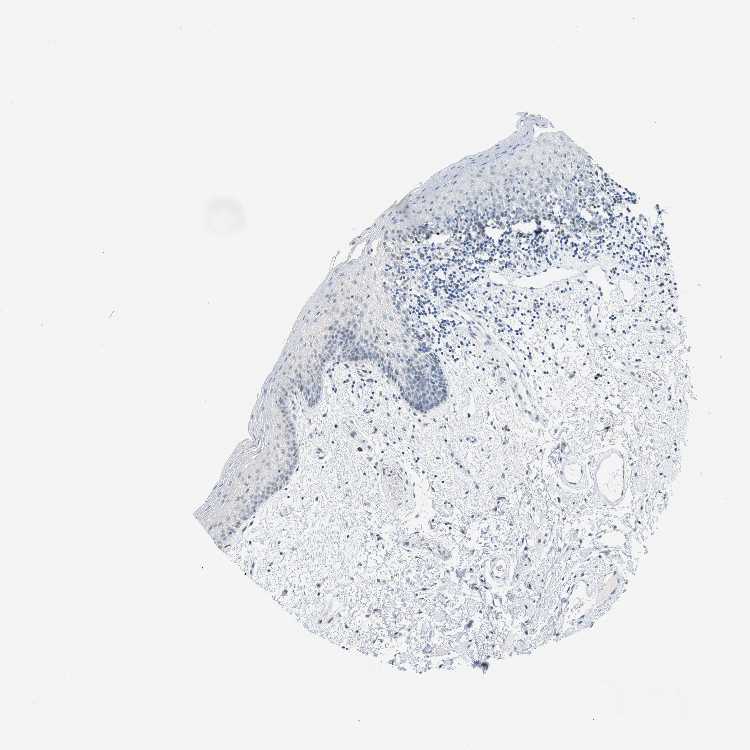

TISSUE PRIMARY DATA ORAL MUCOSA Show tissue menu

ORAL MUCOSA - Antibody stainingi

Antibody staining in the annotated cell types in the current human tissue is reported as not detected, low, medium, or high, based on conventional immunohistochemistry profiling in selected tissues. This score is based on the combination of the staining intensity and fraction of stained cells.

Each image is clickable and will lead to virtual microscopy that enables deeper exploration of all samples and also displays staining intensity scores, fraction scores and subcellular localization as well as patient and tissue information for each sample.

Antibody HPA049808Antibody HPA062476Antibody CAB018351

Squamous epithelial cells LowLowNot detected